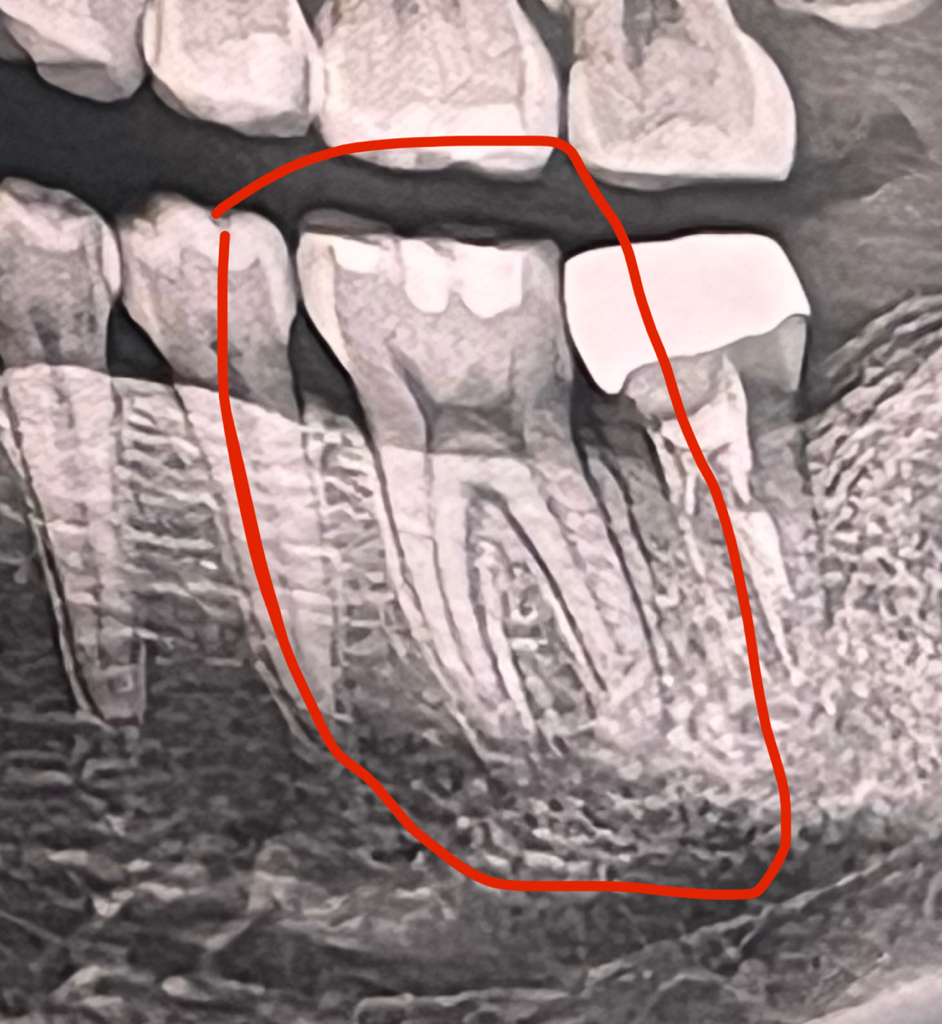

+ 혹시 치료 전 엑스레이, CT촬영 했는데

ct에서는 크랙이 확인 가능할까요?

CT에서는 크게 금이 간치아가 아니면 확인이 힘든경우가 많아요.